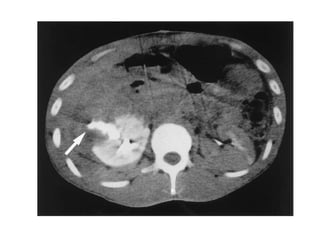

The kidneys can be injured by blunt or penetrating trauma, requiring timely medical evaluation. The kidneys are normally protected by back muscles but can be damaged by severe impacts or objects piercing the skin. Blunt trauma may cause bruising while penetrating injuries like gunshots can enter elsewhere and travel to the kidneys. Most kidney injuries are minor but evaluation with imaging tests like ultrasound or CT scans helps classify the injury and guide management, which may include rest, antibiotics, surgery, or nephrectomy in more severe cases.